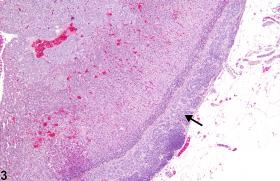

<p>Adrenal gland - Accessory adrenocortical nodule in a male F344/N rat from a chronic study. Accessory cortical tissue within the capsule is composed of nests of cortical cells (arrow).</p>

Adrenal gland - Accessory adrenocortical nodule in a male F344/N rat from a chronic study. Accessory cortical tissue within the capsule is composed of nests of cortical cells (arrow).